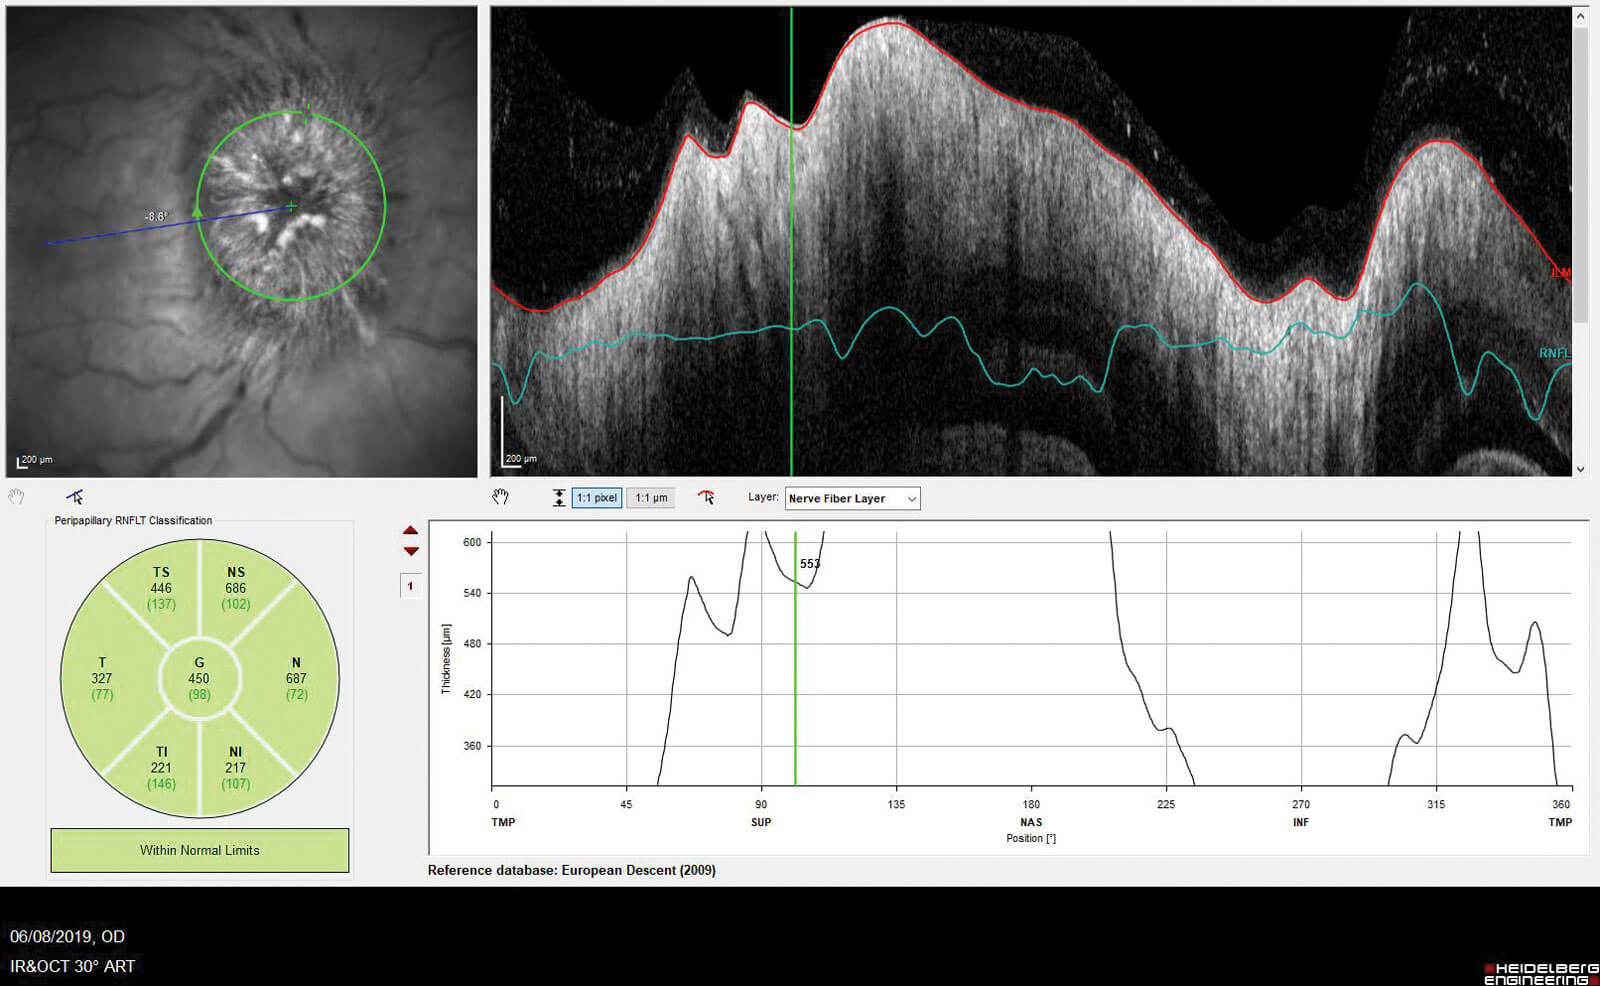

From a photographer’s point of view there are some different optic disc scans that are available to us. Using imaging equipment, such as the Heidelberg Spectralis, we can perform a retinal nerve fibre layer (RNFL) circular scan and a cross-sectional optic nerve head (ONH) scan. The RNFL shows the thickness of the nerve fibre layer and this is helpful in mild cases of papilloedema. However, when the optic disc is moderately swollen or more then this is not helpful, as the OCT technology cannot segment the layers correctly due to the degree of swelling. You can see in Figure 1 that the nerve fibre layer cannot be seen very clearly as the swelling is too great for the machine to pick up the retinal layers, therefore the thickness measurements are not accurate, though they do indicate the swelling in the disc.

Figure 1: RNFL scan showing inaccurate segmentation on an optic disc with papilloedema.